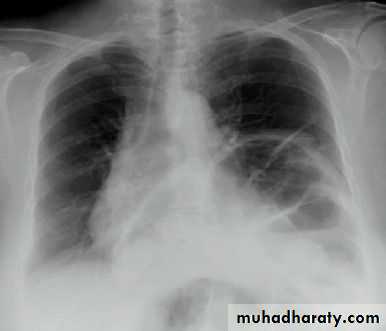

Severe dyspnea with shock